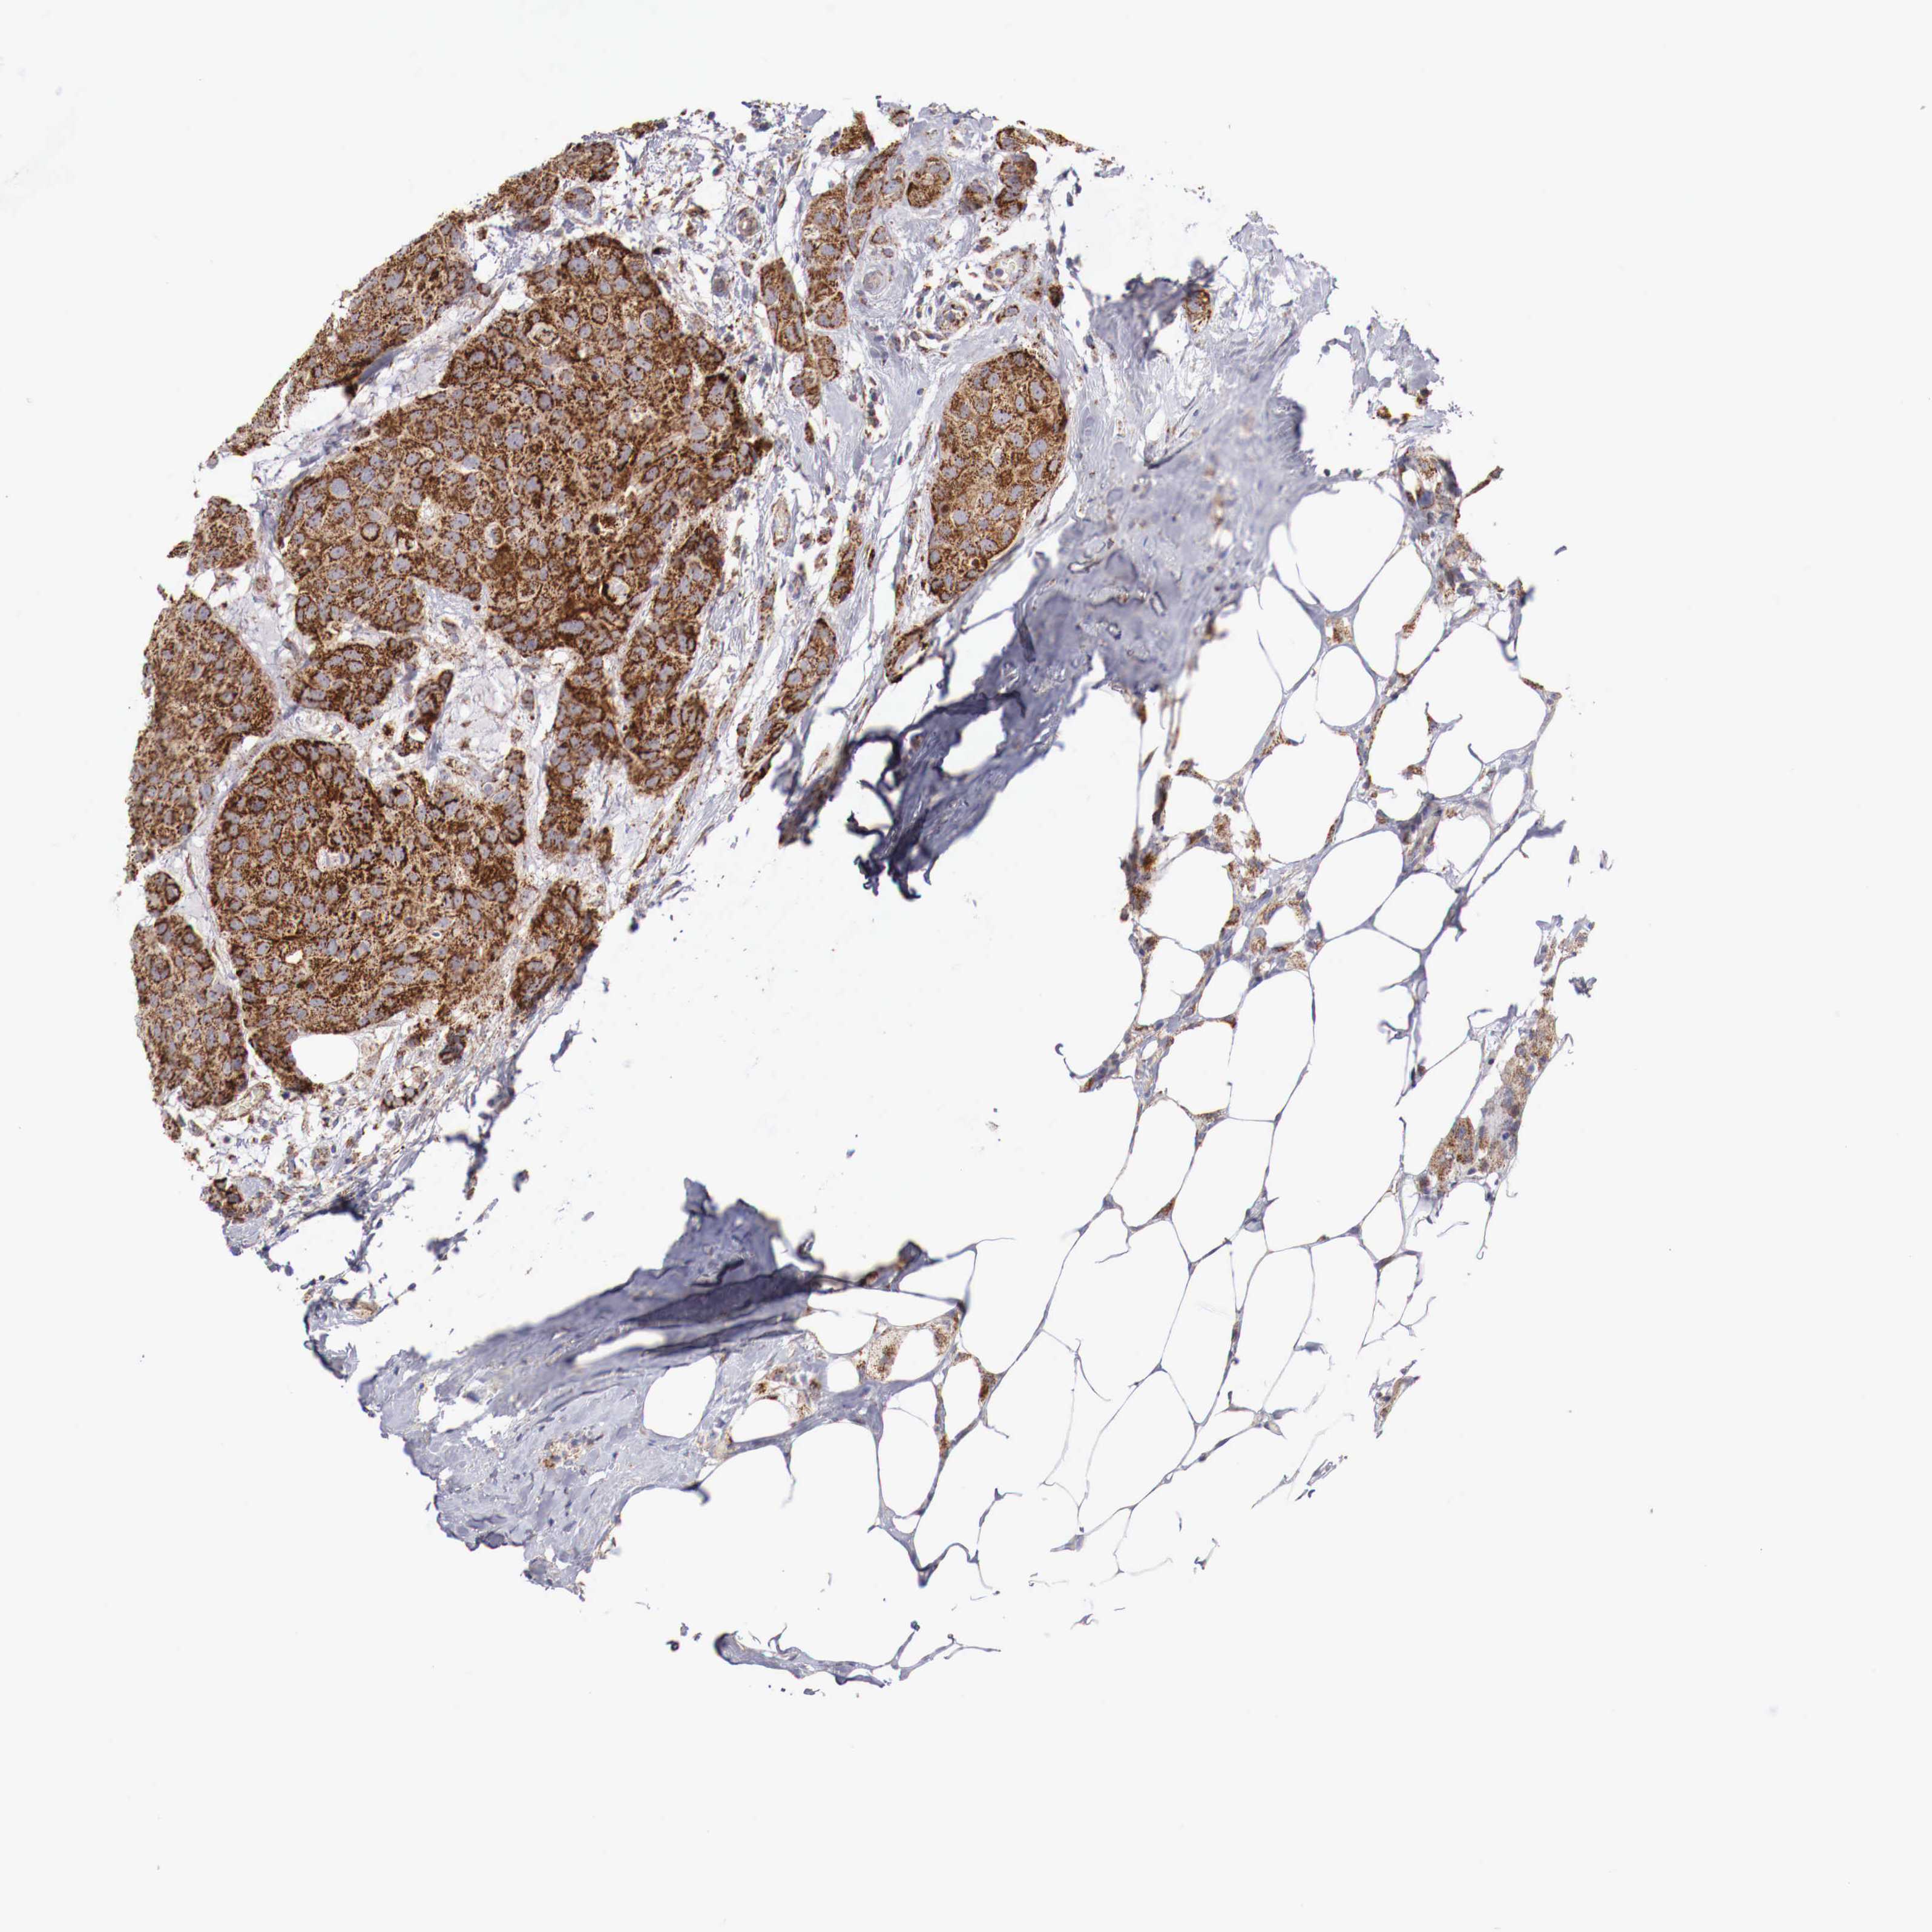

BRCA TCGA BRCA VALIDATION PROTEIN EXPRESSION